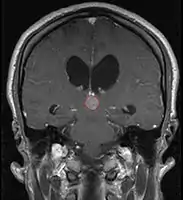

Pineal Gland Tumors

Clinical Presentation

- Determined by the spatial anatomy and direction of growth

- Obstruction of aquaduct: hydrocephalus presenting as headaches, nausea, vomiting

- Compromise of superior colliculus: vertical gaze palsy, pupillary and oculomotor nerve paresis (Parinaud syndrome)

- Progressive growth: cranial nerve neuropathies, hypothalamic dysfunction